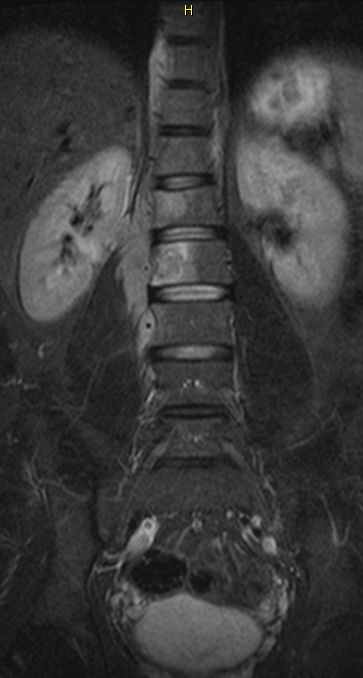

Rezidiv 1 Jahr nach follikulärem Lymphom

MRT